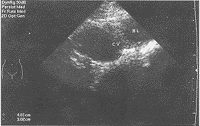

图1 单纯卵巢囊肿:囊壁薄,边界清晰、光滑、内部透声良好(BL-膀胱 CY-卵巢囊肿)

在488例绝经后妇女中检出卵巢囊肿80例(6.1%)。绝经后1~5年39例,6~10年28例,11~15年 9例,16~20年4例。其中单纯卵巢囊肿(指囊壁薄,边界清晰、光滑,内部透声良好) 57例(图1)。囊肿直径3~8 cm 74例(92.5%),9~11 cm 5例(6.3%),最大19 cm 1例(1.3%)。盆腔检查发现29例直径均大于4 cm,4 cm以下51例均为超声检查发现。因临床怀疑恶性肿瘤或患者要求手术探查23例,均为浆液性囊腺瘤、乳头状瘤、囊性纤维瘤、畸胎瘤和单纯囊肿。囊肿内无分隔、直径小于5 cm的患者,同意以超声随访观察者57例,其中29例经雌激素疗法1~13个月囊肿消失,21例1~3年内自然消失,4例2年无变化,3例已观察1年仍在随访。